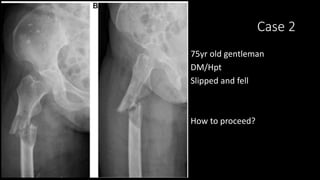

Case 2

75yr old gentleman

DM/Hpt

Slipped and fell

How to proceed?